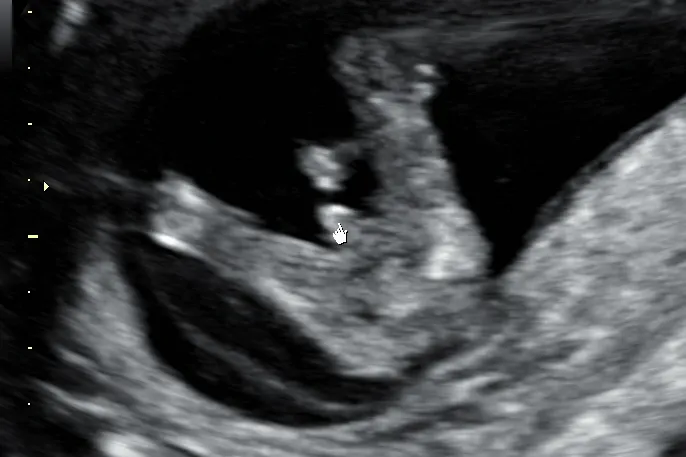

Czym jest "The Nub Theory" i czy można jej ufać?

Wczesna ocena płci w pierwszym trymestrze często opiera się na tzw. "the nub theory", czyli teorii guzka płciowego. Polega ona na analizie kąta nachylenia małego guzka, który w przyszłości rozwinie się w narządy płciowe. Jeśli kąt nachylenia guzka względem kręgosłupa płodu wynosi powyżej 30 stopni, sugeruje to chłopca. Natomiast ułożenie bardziej równoległe do kręgosłupa, z kątem poniżej 30 stopni, wskazuje na dziewczynkę. Muszę jednak zaznaczyć, że jest to jedynie prognoza, a nie pewna diagnoza.

Jakie jest ryzyko pomyłki na tak wczesnym etapie?

Skuteczność oceny płci w pierwszym trymestrze, bazując na "nub theory", szacuje się na około 75-90%. Jak widać, ryzyko pomyłki na tak wczesnym etapie rozwoju płodu jest wciąż dość znaczące. Narządy płciowe nie są jeszcze w pełni wykształcone, a guzek płciowy u obu płci wygląda początkowo bardzo podobnie. Dlatego zawsze podkreślam moim pacjentkom, że wczesna prognoza jest fascynująca, ale należy do niej podchodzić z pewną rezerwą.